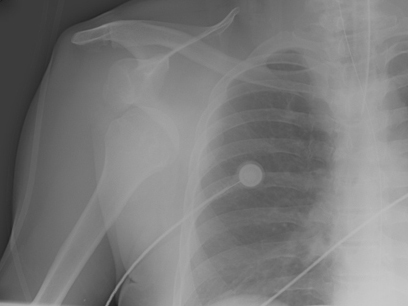

Anteroposterior x-ray view of a shoulder showing an anteroinferior dislocation

Personal collection of Dr Paul Novakovich